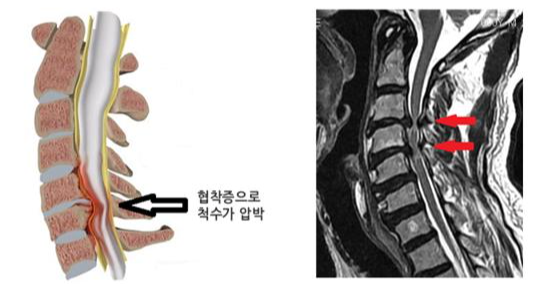

증상의 심각성과 조합은 개인마다 크게 다를 수 있다는 점에 유의하는 것이 중요합니다. 어떤 사람들은 가벼운 불편함을 느낄 수도 있고, 다른 사람들은 쇠약해지는 통증과 심각한 기능 상실을 겪을 수도 있습니다. 더욱이, 드물지만, 경추 추간판 탈출증이 척수를 압박할 만큼 커지면 경추 추간판 탈출증이 경추 척수병증과 같은 더 심각한 상태로 이어질 수 있으며, 협응 장애, 보행 장애, 극단적인 경우에는 자세 변화 등의 증상이 나타날 수 있습니다.

경추 추간판 탈출증은 목 부위에 있는 추간판의 내부 젤 같은 수핵이 외부 섬유 고리인 섬유테의 찢어짐을 통해 돌출될 때 발생합니다. 이 탈장은 인근 신경이나 척수에 영향을 미쳐 강도와 성격이 다양할 수 있는 다양한 증상을 유발할 수 있습니다. 이러한 증상을 이해하는 것은 조기 발견과 효과적인 관리에 매우 중요합니다.